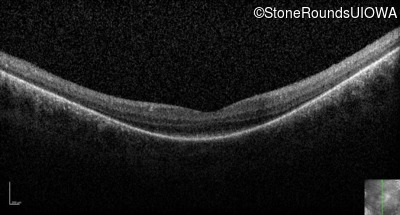

Optical Coherence Tomography - Left - 20/80 -1

Exemplar / OCT Stack